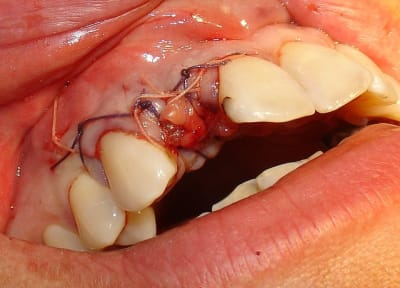

Tiens pour agrémenter! Cet Après midi une extraction implantation. Je n'ai pas oser la mise en charge immédiate si certains l'aurait fait lachez vous.

J'ai fait sauter la table vestibulaire exprès car je ne vois pas comment elle aurait pu etre vascularisée et à part me faire un séquestre osseux et des ennuis j'ai reconstruis.

Regardez les images;

Si certains n'auraient pas extrait argumentez pour traiter en palatin et la felure englobé par le granulome m^me si ce n'est pas mis en évidence sur le scan.

En plus vous voyez le nouvel implant Leone et son indication majeure, c'est vrai que sa mise en place est super aisée, surtout comme celà en palatin.